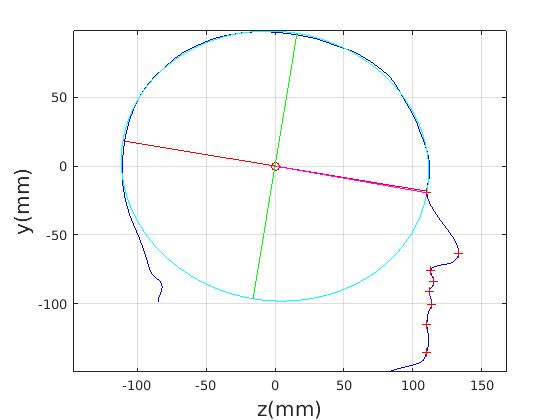

8 A case study of cranial profile model use for intervention outcome evaluation

In this section we take a sample of 25 boys, who are craniofacial craniosynostosis patients, 14 of which have undergone one type of corrective procedure (BS) and the other 11, another corrective procedure (TCR). Providing that the heads are sufficiently symmetrical and are amenable to ellipse fitting, we can parameterise all of these patients’ heads using our scale-normalised craniofacial profile model (2D model with face cropped out). We can then plot their pre-operative and post-operative parametrisations and compare them with the parameterisations of the 100 training examples. The expected result is that the parameterisations should show the head shapes moving nearer to the mean of the training examples. It also reveals which of the dominant modes of shape variation are most affected. The results are shown in figures 31 and 32.

For the BS patient set, the Mahalanobis distance of the mean pre-op parameters (red triangle in Fig. 31) is 4.670, and for the mean post-op parameters (blue triangle) is 2.302. For shape parameter 2 only these figures are 4.400 and 2.156.

For the TCR patient set, the Mahalanobis distance of the mean pre-op parameters (red triangle in Fig. 32) is 4.647, and for the mean post-op parameters (blue triangle) is 2.439. For shape parameter 2 only these figures are 4.354 and 2.439. We note that most of this change occurs in parameter 2, which corresponds to moving height in the cranium from the frontal part of the profile to the rear. In these figures we excluded one patient, who preoperatively already had a near-mean head shape (see red cross near to the origin in Fig. 32, so any operation is unlikely to improve on this (but intervention is required in order to relieve potentially damaging inter-cranial pressure).

It is not possible to make definitive statements relating to one method of intervention compared to another with these relatively small numbers of patients. However, the cranial profile model does show that both procedures on average, lead to a movement of head shape towards the mean of the training population. An example of analysis of intervention outcome for a BS patient is given in Fig. 33 and a TCR patient is given in Fig. 34. The particular example used is highlighted with circles on figures 31 and 32 to indicate pre-op and post-op parametrisations. To our knowledge this is the first use of statistical 3D craniofacial shape models in a clinical study.